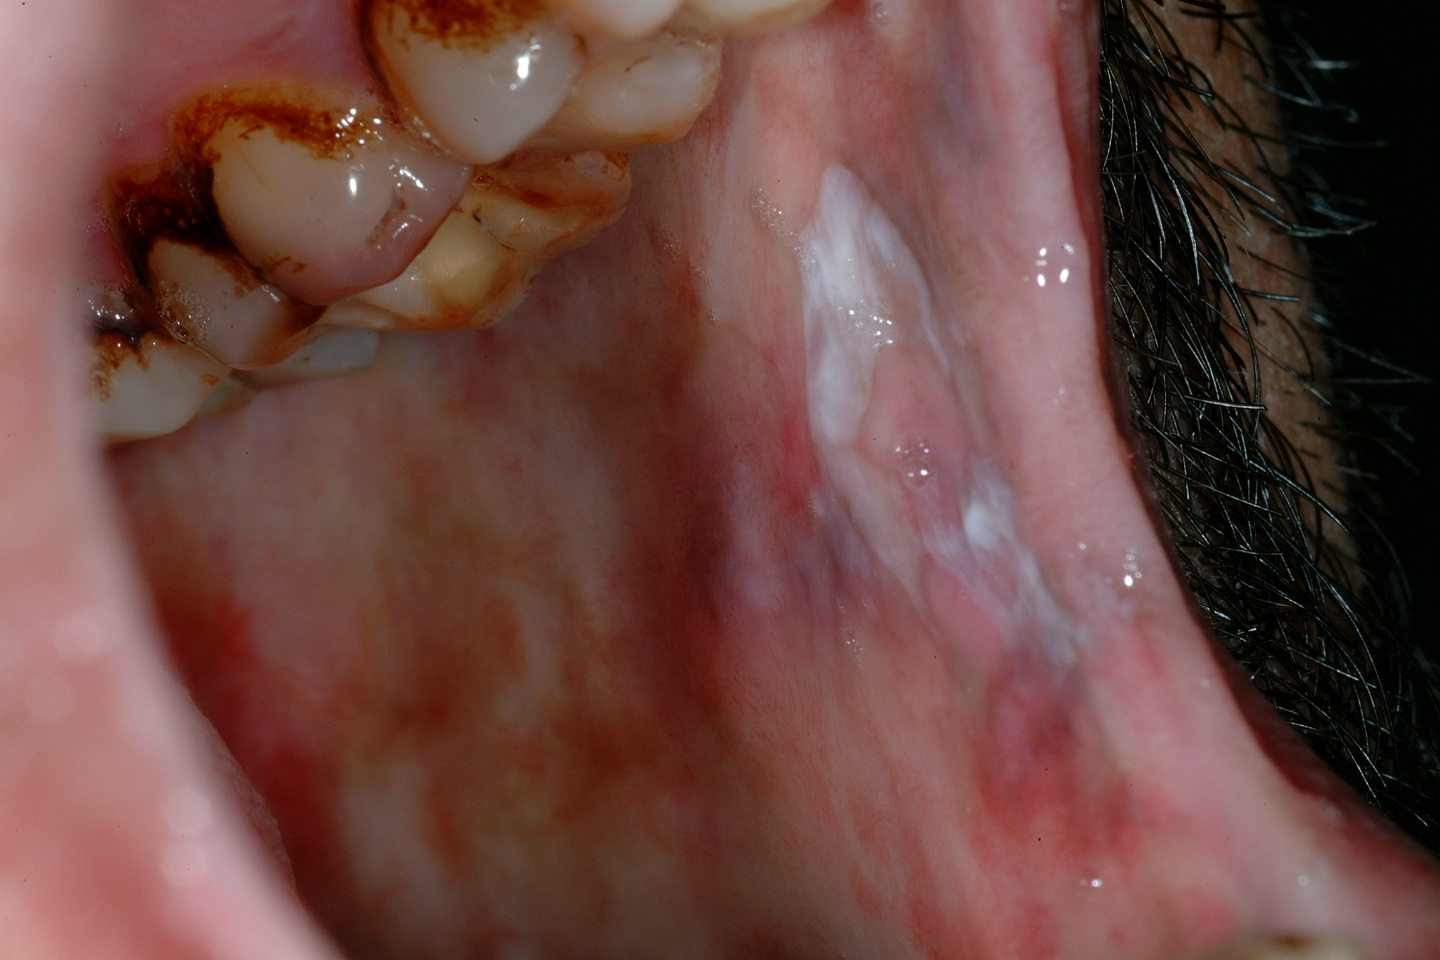

Submucous fibrosis

Submucous fibrosis is a progressive lesion forming bands of scarred tissue (fibrosis) beneath the mucosa (see Figure 4). Submucous fibrosis is associated with epithelial dysplasia and a quoted risk for malignant transformation of approximately 5 %. The strands of scarred tissue (fibrosed bands) can lead to severe trismus (difficulty opening the mouth). Submucous fibrosis is strongly associated with chewing habits of areca nuts, gutka and betel – common on the Indian subcontinent.